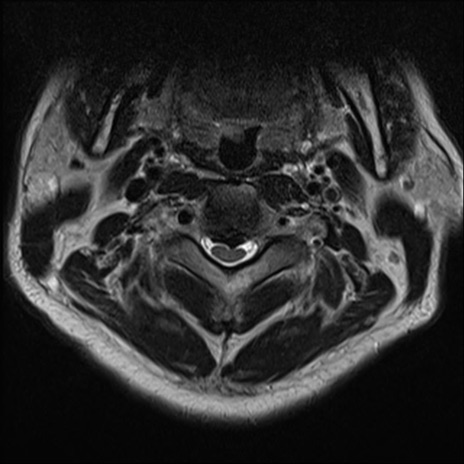

【整形】TIPS症例7 頚椎MRI T2WI(横断像)

頚椎MRI

矢状断像と横断像